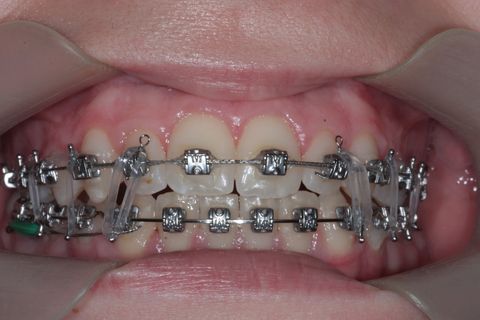

Montagem de fixo

Uso do Twin Force por aproximadamente 3 meses

Twin Force